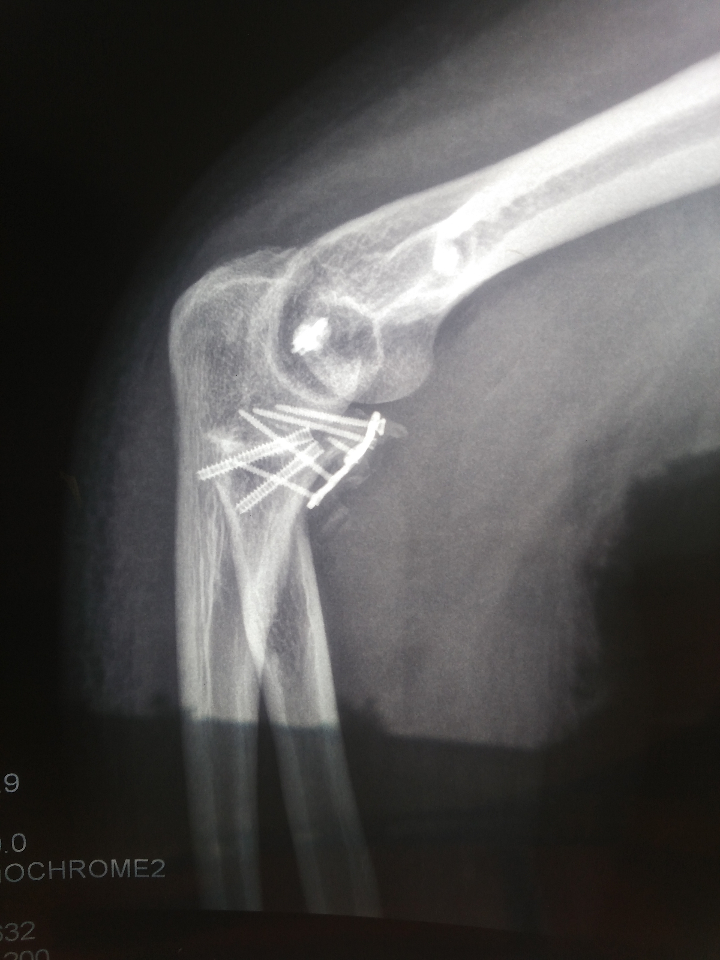

肘关节恐怖三联征还有骨化

手术后52天了,医生说要使劲锻炼伸直弯曲和旋转,但康复科的医生说又不能太用力锻炼,以免加重骨化。现在被动伸直几乎能到0度不过很痛,弯曲被动能到90-100吧,旋转很差,现在很担心手以后会废掉我才28啊,不能干活以后怎么养家糊口啊,心里很纠结不知道说用力锻炼好还是不用力锻炼好!!请吧友们指点指点!

手术后快两个月了,现在旋转、伸直、弯曲恢复的不理想,好担心以后这手废掉

我的钉子和钢板医生也说不取,你的伸直和弯曲和旋转怎么样啊?

好好锻炼吧,18年5月我也是恐怖三联征+异位骨化+旋转不行,做完手术两个多月自己做康复没效果,接着去做医院做康复训练,目前手的弯曲还好,就是旋转太好,手伸直再旋转也有疼痛感